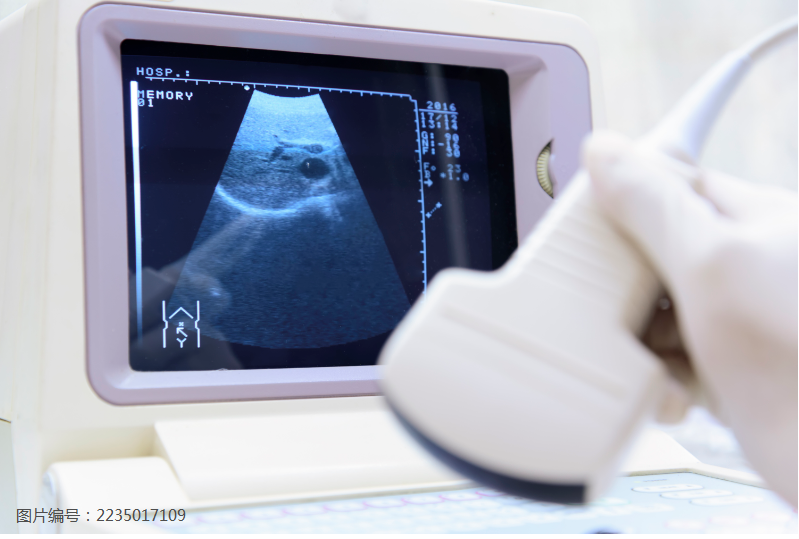

正在给患者检查的张发萍,只见她拿起探头放到患者身体上,眼睛紧盯着荧屏影像一言不发。探头被张发萍稳稳地握在手里,在患者的身上几个部位来回扫描了数次。

超声科的诊疗不像临床医生抢救病人惊心动魄。这里的医生必须静下心来,用鹰一般锐利的眼睛捕捉荧屏上的蛛丝马迹。敏锐的观察配合巧手,准确的手法几乎占据了诊断结果正确率的60%。

“简单来说,病症就是‘地雷’,医生要用手里的探测器把‘雷’探出来,探不到就是漏诊,我们的彩超检查就是医生的窗户。”

据了解,张发萍熟练精准的手法,得益于数十年如一日的一丝不苟,在同事眼中,这个总是笑眯眯,说话和气的张医生,工作起来简直“不要命”,一入检查室,精力便开始高度集中。同科室的医生都开玩笑说:“哪怕外面天塌了,张医生拿着探测器的手也不会抖一下。”

“胎宝宝的健康对每个家庭都很重要。检查必须专心,所以,我只要一开始工作就什么都不想,心就只有那一小块荧屏大小,一定要看得清清楚楚才罢休。”张发萍说。